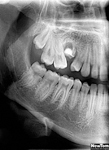

3D DVT - NewTom

Je speciální zubní digitální tříprostorový tomograf (3D), který umožňuje na základě jediného

snímkování vytvořit všechny typy RTG zobrazení, které jsou pro lékaře potřebné. Díky používané technologii tzv. „kuželového paprsku“ a speciálním senzorům je

výrazně zmenšená dávka záření - o více jak 80% proti klasickému CT vyšetření. To je významné zejména u dětí. Pomocí tohoto přístroje je možné zjisti skutečnou situaci v čelistních kostech pacienta tedy množství kosti - můžeme změřit skutečnou šířku i výšku kosti, i kvalitu kosti (hustotu) v místě uvažované implantace. 3D (tříprostorové) zobrazení umožňuje zvýšit prostorovou představu operatéra ještě před vlastní operací a zároveň pacientovi lépe objasnit a ukázat oblast plánovaného zavedení implantátu.

Pacient „neumí číst“ RTG snímky, ale díky 3D zobrazení vidí „svoji skutečnou čelist“

- např. jak je nízká či úzká, vidí průběh nervu nebo velikost čelistní dutiny, což mu umožní i pochopení nutnosti v některých případech provést pomocné zákroky ještě před vlastním zavedením implantátu (viz. kostní štěp, sinus lift, kostní granulát...).

Vyšetření pomocí tohoto přístroje používáme i ve stomatochirurgii (zlomeniny čelistí, zuby moudrosti, cysty, onemocnění čelistního kloubu), ortodoncii (retinované zuby, nadpočetné zuby), parodontologii atd.

NewTom Giano

Jedná se o nejnovějším přístroj ze skupiny dentálních hybridních CBCT (3D) + 2D (pan i ceph) systémů. Opět umožňuje na základě jediného snímkování vytvořit všechny typy RTG zobrazení, které jsou pro lékaře potřebné. Používaná technologii tzv. „kuželového paprsku“ a speciální senzory pro minimální zátěž při snímkování pacienta.

Vyšetření pomocí tohoto přístroje (nebo

3D DVT - NewTom) a získaná data používáme

pro každou implantaci, dále ve stomatochirurgii (zlomeniny čelistí, zuby moudrosti, cysty, onemocnění čelistního kloubu), ortodoncii (retinované zuby, nadpočetné zuby), parodontologii atd.